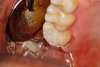

Figure 8A is a radiograph revealing deep root caries previously restored temporarily by a resident at the AEGD Residency Program clinic with glass ionomer utilizing a lateral rather than occlusal approach. After the glass ionomer failed to adhere, another resident again attempted a lateral approach that resulted in the restoration shown in Figure 8B. A third resident had success with an occlusal approach, removing a failed occlusal composite to access the distal  (Figure 9). This attempt was successful both in the preparation of the lesion and in the placement of a dual- cure bulk-fill flowable (Bulk EZ Plus, Zest Dental Solutions; alternatively: HyperFIL®, Parkell; Fill-Up!, Coltene) extruded through a bendable needle (Figure 10). Figure 11 shows the final preparation after tissue removal was accomplished with rotary gingitage; note that this was performed with the rubber dam in place. An air abrasion device (Groman Etchmaster, Groman Dental; alternatively: PrepStart H2O, Zest Dental Solutions; Bioclear Blaster, Bioclear) was used with potassium bicarbonate to remove biofilm prior to acid etching (Figure 12). Phosphoric acid 37% was utilized in a total etch fashion (Fig- ure 13 and Figure 14) for 20 seconds. Figure 15 shows the universal bond (Scotchbond Universal, 3M; alternatively: All-Bond Universal®, BISCO; Prelude One, Danville Materials) with metha- cryloyloxydecyl dihydrogen phosphate (MDP) being scrubbed into the cavity for 20 seconds. After air thinning for 20 seconds, the adhesive was light cured for 40 seconds at 1,200 mw/cm2power density (Figure 16).

Fig 9. View of existing occlusal composite to be removed to access the distal lesion on tooth No. 2.

Figure 9

Fig 10. Occlusal approach was successful in the placement of a dual-cured bulk-fill flowable. Note the depth of box form.

Figure 10